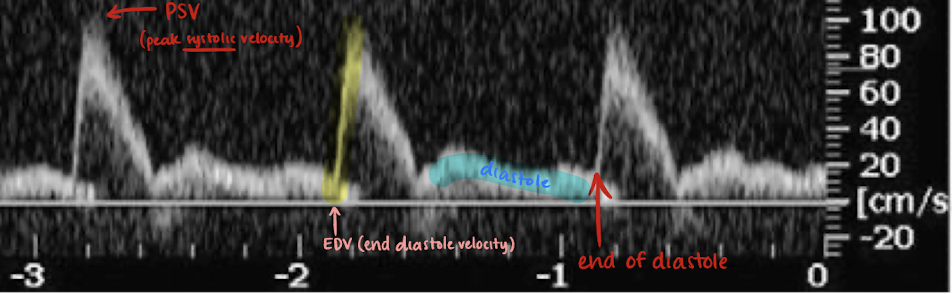

AO Doppler waveform

high and low resistant waveform; sharp brisk upstroke; significant reduced diastolic flow; no spectral broadening

PSV and EDV

PSV=peak systolic velocity

EDV=end diastole velocity